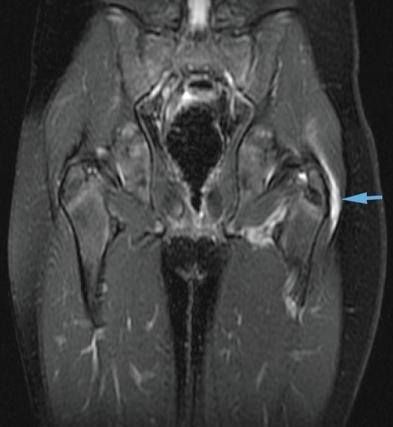

Trochanteric Bursitis

This is inflammation of the trochanteric bursa.This bursa is at the top, outer side of the femur. It has the function of working as a shock absorber and as a lubricant for the movement of the muscles adjacent to it, especially the Ilio-Tibial Band (ITB). This is a strong sheet of tissue that runs from the Pelvis all the way past the knee to insert into the Tibia.

The ITB can get tight over time or due to general deconditioning and poor gait. The ITB will cause friction over the Trochanteric Prominence causing the Bursa to get inflamed.